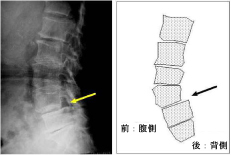

巻き爪、タコ、魚の目等があると症例に示すように、様々な症状を呈します。

早いうちに処置をして快適な生活を心がけましょう。